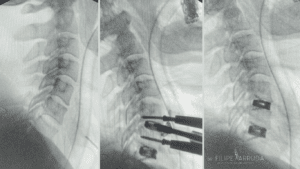

Nesse vídeo de 1 minuto super explicativo explico com muita clareza com imagens qual a diferença de um abaulamento, profusão e uma hérnia de disco extrusa.

Cirurgião da Coluna Vertebral